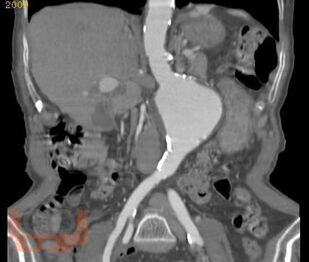

Учебное пособие подготовлено в соответствии с ООП и учебным планом по дисциплине «Пропедевтика внутренних болезней» для обучающихся по специальности 31.05.01 «Лечебное дело». В учебном пособии изложены современные представления о болевом абдоминальном синдроме при заболеваниях органов пищеварительной системы, необходимого для обучающихся при изучении дисциплины «Пропедевтика внутренних болезней». Учебное пособие оснащено тестовыми заданиями и ситуационными задачами различной степени сложности для самоконтроля знаний с эталонами ответов. Учебное пособие предназначено для самостоятельной внеаудиторной работы обучающихся по специальности «Лечебное дело».